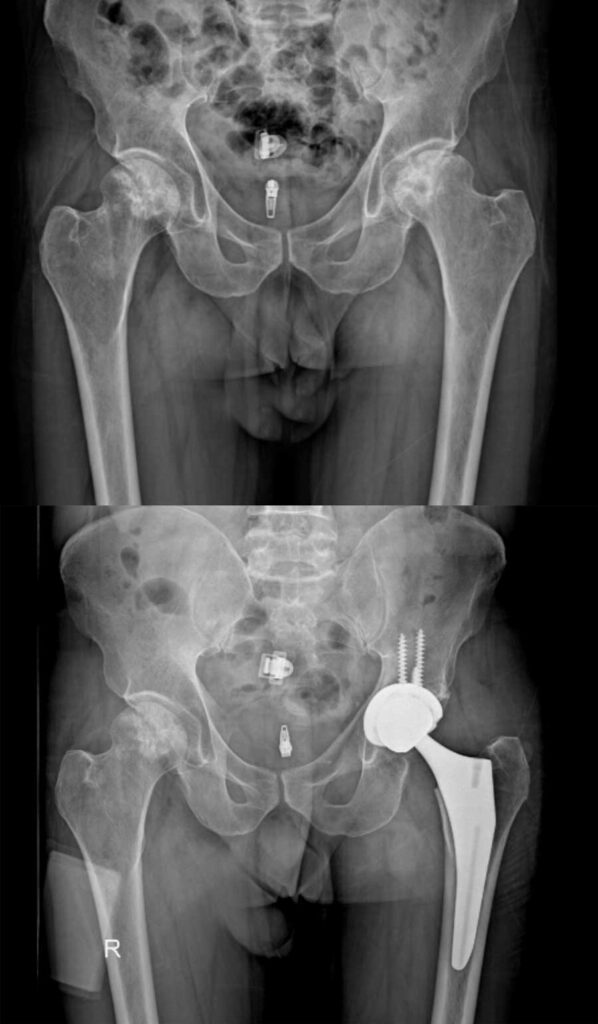

عکس تعویض مفصل لگن

برای آشنایی با تصاویر واقعی رادیوگرافی لگن قبل و بعد از جراحی، عکس تعویض مفصل لگن چند بیمار در زیر وجود دارد. با کلیک بر روی هر کدام از آنها تصویر بزرگتر و کامل را خواهید دید.